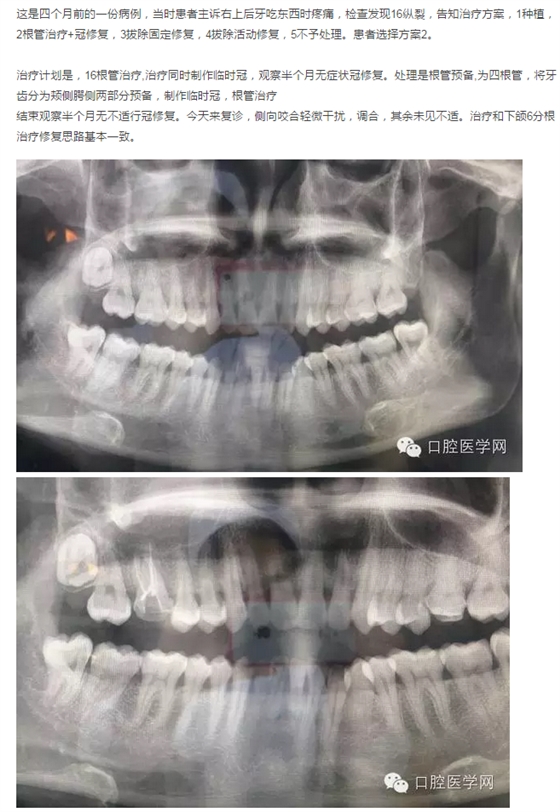

首頁各類病例 1例16縱裂的治療

1例16縱裂的治療